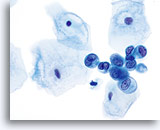

Abnorme Endozervikalzellen (NOS)

Abgebildet ist ein „Sheet“ von Endozervikalzellen mit leicht gestörter Architektur, leichter Dreidimensionalität der Gruppe, reichlichem Zytoplasma, gleichmäßigem, blandem Chromatin und prominenten Nukleoli in jedem Kern. Die Diagnose einer Atypie kann durch die Dreidimensionalität der Gruppe und die leicht gestörte Architektur nahe gelegt werden.

60X

Biopsie – Entzündliche Atypie

Abnorme Endozervikalzellen (NOS)

Abgebildet ist ein „Sheet“ von Endozervikalzellen mit leicht gestörter Architektur, leichter Dreidimensionalität der Gruppe, reichlichem Zytoplasma, gleichmäßigem, blandem Chromatin und prominenten Nukleoli in jedem Kern. Die Diagnose einer Atypie kann durch die Dreidimensionalität der Gruppe und die leicht gestörte Architektur nahe gelegt werden.

60X

Biopsie – Entzündliche Atypie